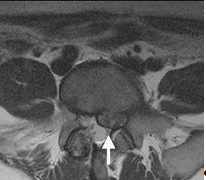

Spinalkanalstenose

Die Spinalkanalstenose ist eine zunehmende dynamische Einengung des Wirbelkanals auf Bandscheibenniveau durch überwiegend degenerative Veränderungen der Bandscheibe, der Wirbelkörperendplatten, der Zwischenwirbelgelenke sowie der umgebenden Bandstrukturen mit und ohne begleitende Instabilität des betroffenen Bewegungssegmentes. Die Lendenwirbelsäule ist hiervon häufiger als die Halswirbelsäule betroffen.

In Abhängigkeit der Ausprägung der Stenose kommen hier minimalinvasive Operationen als auch stabilisierende Operationen in Frage.